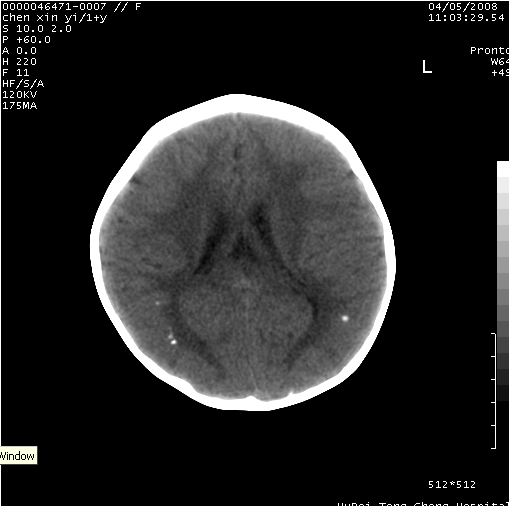

以下是引用zhangzhongshou在2008-4-9 12:54:00的发言:[br]请结合病史,有以下可能1、炎性肉芽肿钙化(含结核)2、寄生虫钙化(含脑囊虫)3、其他良性钙化性病变